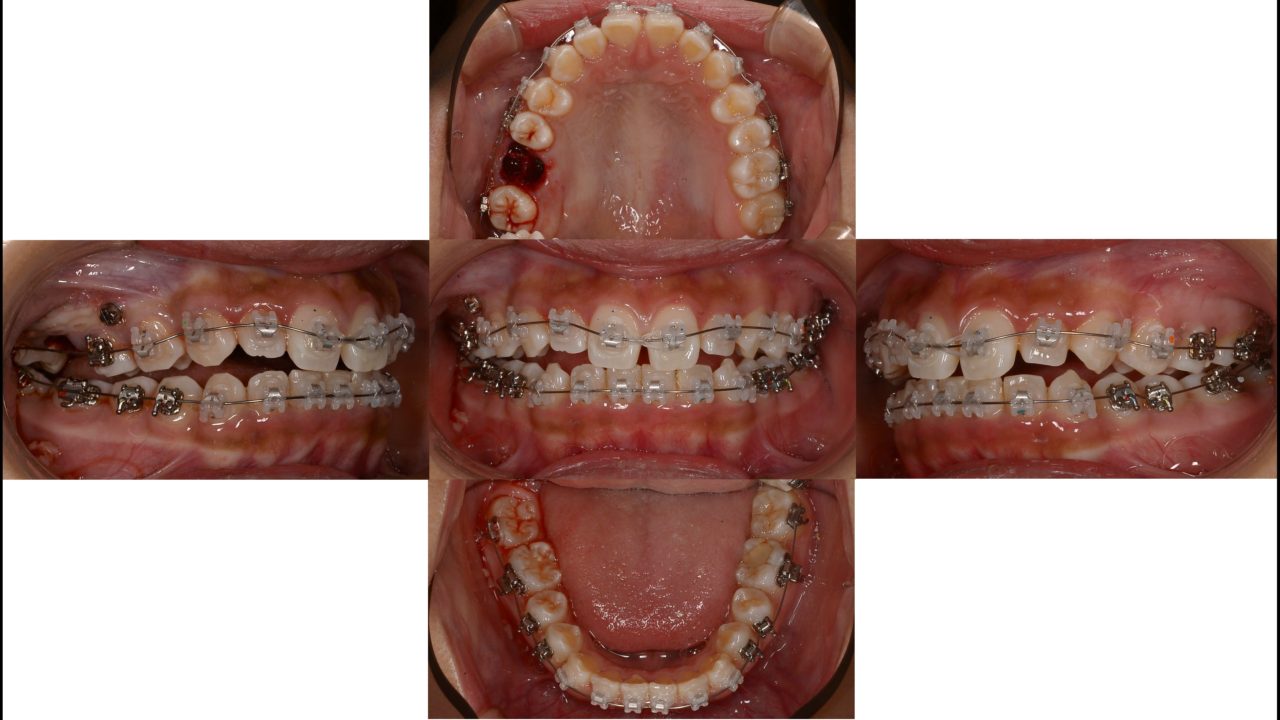

2021.10.11 治療開始9か月

2022.3.14 矯正治療終了

| 備考 | 右上第1大臼歯の自発痛で来院されました。 マイクロスコープ下の精密根管治療を行えば、十分改善する見込みはありました。 しかし、14歳と若く、長期的な予後は不安でした。 前歯の歯列、咬合不正があったため、全顎矯正を提案しました。 全顎矯正ができれば、予後不良な右上第1大臼歯を抜歯して、親知らずを活かせます。 そうなれば、神経の死んだ歯はなくなり、歯の数も減りません。 14か月で矯正治療が終了したため、まだ親知らずは萌出していませんが、レントゲン的にはいい位置に来そうです。 注意深いメインテナンスを行っています。 |